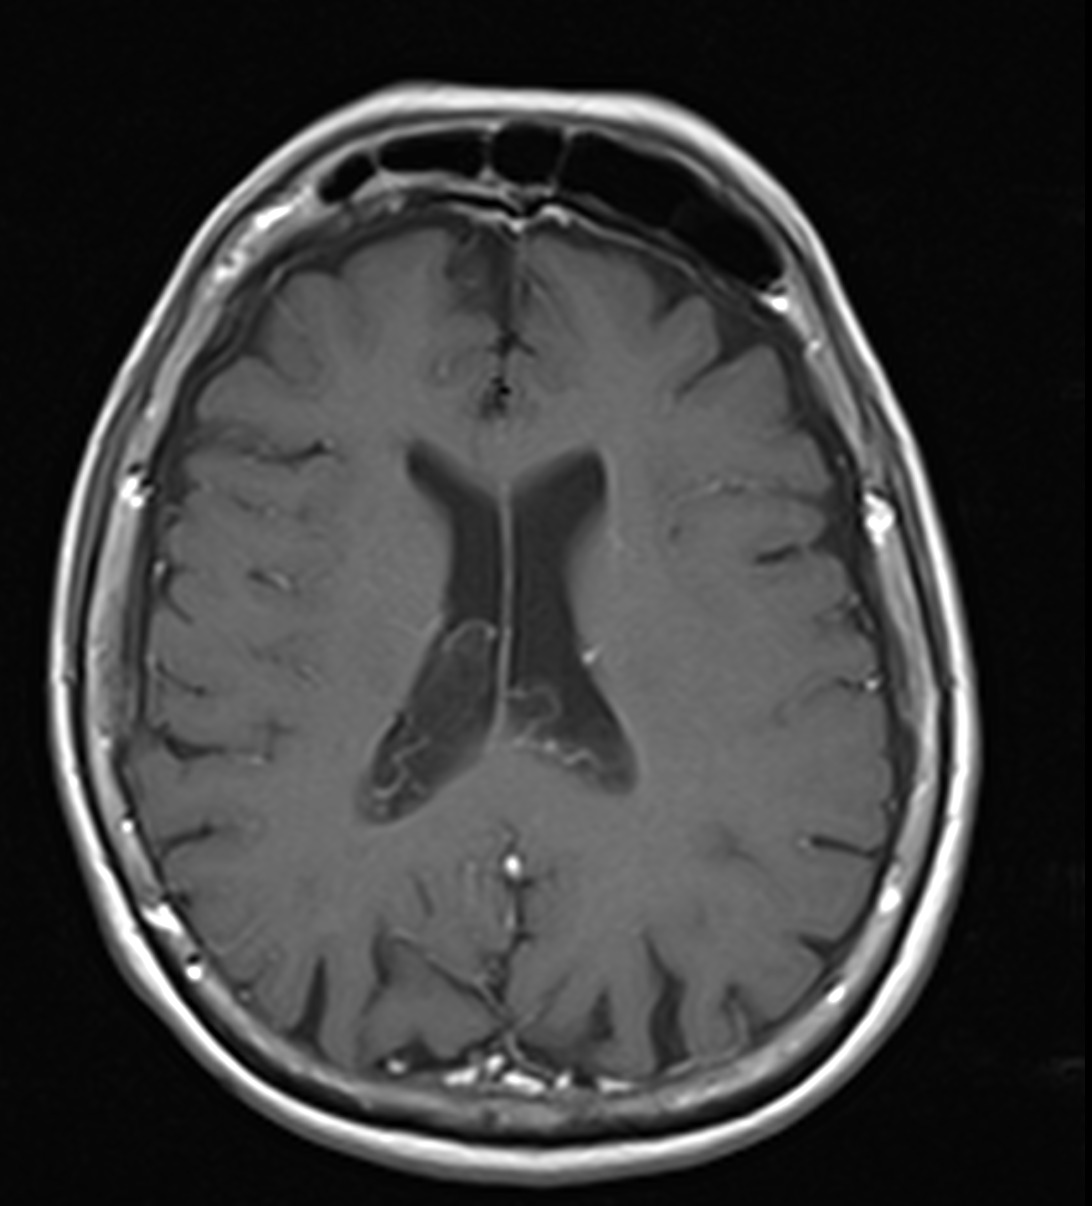

✔ Lesiones intraventriculares

✔Bilaterales

✔65% restringen en la secuencia de difusión

✔ Realce variable posterior a la administración de medio de contraste

✔ No hay edema del parenquima adyacente

NO DEBEN CONFUNDIRSE CON LESIONES TUMORALES INTRAVENTRICULARES!!!!